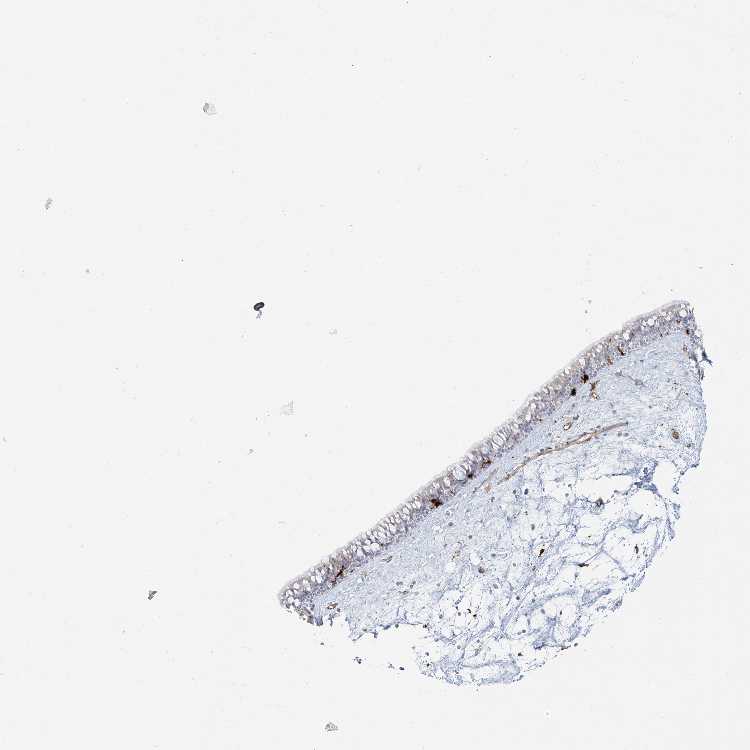

TISSUE PRIMARY DATA NASOPHARYNX Show tissue menu

NASOPHARYNX - Antibody stainingi

Antibody staining in the annotated cell types in the current human tissue is reported as not detected, low, medium, or high, based on conventional immunohistochemistry profiling in selected tissues. This score is based on the combination of the staining intensity and fraction of stained cells.

Each image is clickable and will lead to virtual microscopy that enables deeper exploration of all samples and also displays staining intensity scores, fraction scores and subcellular localization as well as patient and tissue information for each sample.

Antibody HPA043151Antibody CAB015400Antibody CAB034021

Basal cells -Medium-

Ciliated cells (cell body) -Not detected-

Ciliated cells (cilia axoneme) -Not detected-

Ciliated cells (ciliary rootlets) -Not detected-

Ciliated cells (tip of cilia) -Not detected-

Goblet cells -Not detected-

Respiratory epithelial cells Low-Not detected